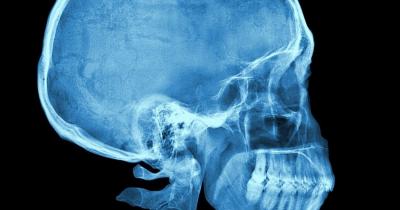

या शोधातून ऐतिहासिक कागदपत्रांच्या दाव्याची पडताळणी केली जाईल. शास्त्रज्ञांनी १२ मानवी मृतदेहांचे शीर कापले आहेत. हे शीर फॉर्मलडीहाइडमध्ये ठेवण्यात आले होते. यानंतर नवीन १६ शवांचे सीटी स्कॅन करण्यात आले. त्यानंतर काही जिवंत माणसांच्या जबड्यांचा एमआरआय करण्यात आला.

या तपासात गालातील स्नायूंमध्ये आणखी एक खोल थर आहे, जो रचनेच्या आधारावर इतर दोन स्तरांपेक्षा वेगळा आहे. हा स्नायू प्रत्यक्षात हाडासारखा दिसतो. हा नवीन स्नायू हाडासारखा दिसण्याचे कारण म्हणजे त्याच्या आजूबाजूला हाडे असतात. ज्यांना गालाची हाडे(Cheek Bones) म्हणतात.

हा कानाजवळ समोरच्या बाजूला स्थित आहे. शास्त्रज्ञांनी खालच्या जबड्याच्या अगदी वर त्रिकोणी आकाराचा फुगवटा देखील पाहिला, जो या नवीन स्नायूमुळे तयार झाला होता. जे या नवीन स्नायूमुळे तयार झाले आहे. हा स्नायू जबड्याला उघडझाप करण्यासाठी, हालचालींसाठी मदत करतो.